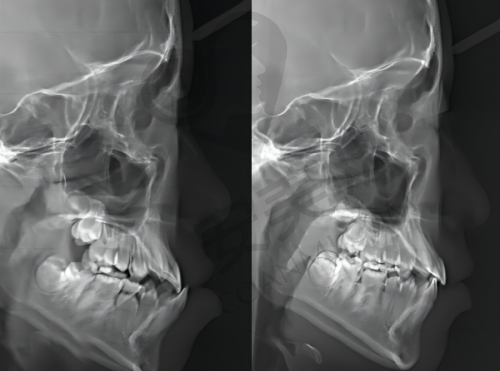

首先,医院拥有精良的口腔诊疗设备和技术。这些设备和技术能够为种植牙手术提供严谨的诊断和治疗方案,提高手术的成功几率和成效。例如,精良的口腔CT设备可以清晰地显示患者口腔内部的骨骼结构和牙齿情况,帮助医生制定更加精细的种植方案。